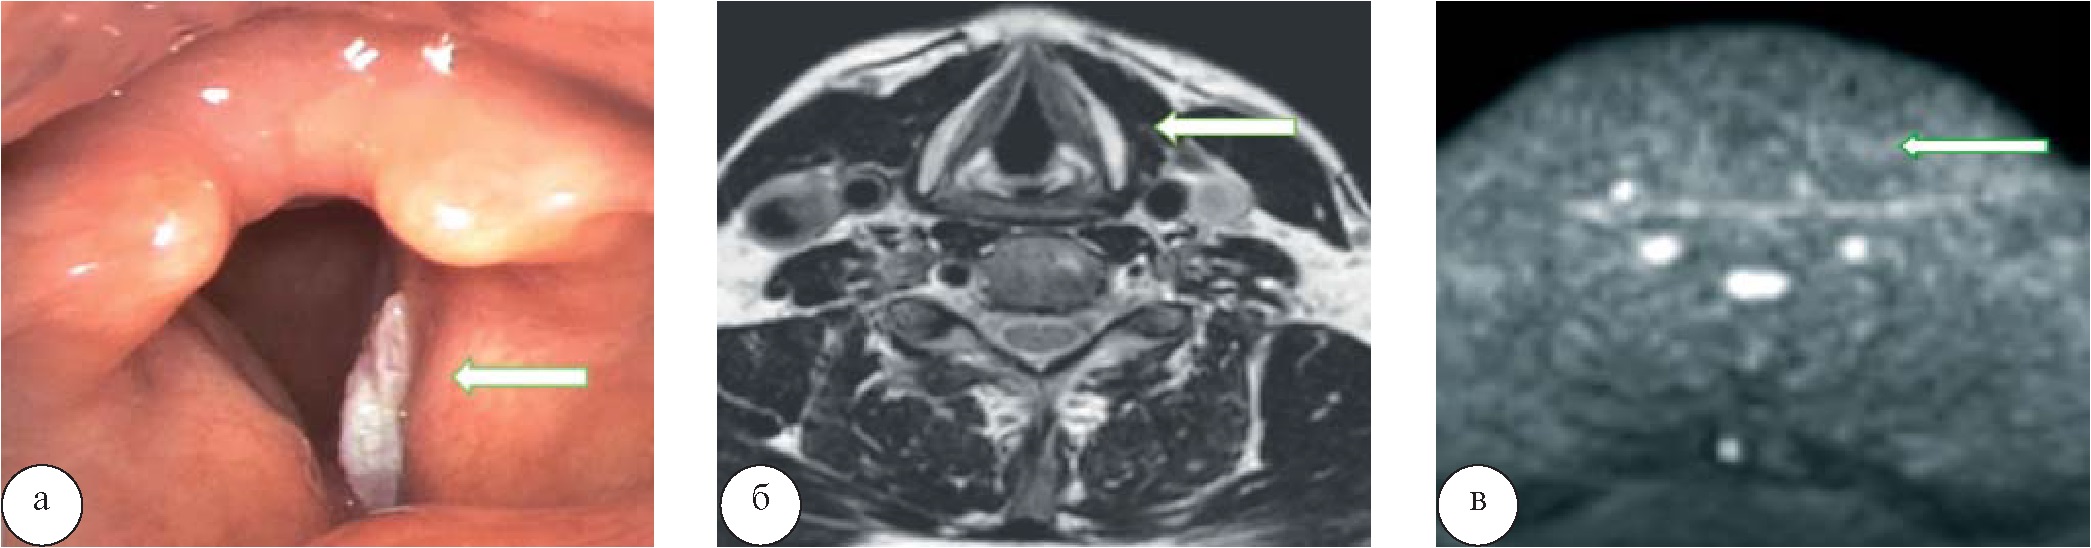

Результаты и их обсуждение. При выполнении КТ у 50 (92,5%) человек было выявлено первичное образование, в половине случаев без визуализации четкого внутреннего его контура (46,2%). У 49 (90,7%) пациентов визуализировалось накопление контрастного вещества образованием, у 10 (18,5%) человек отмечалась инвазия в прилежащие мягкие ткани, у 4 (7,4%) пациентов – деструкция хрящей гортани (рис. 1), регионарные метастазы в шейные лимфатические узлы прослеживались у 29 (53,7 %) человек.

Рис. 1. Рак гортани. При ларингоскопии (а) отмечается крупное образование правой половины гортани (стрелка). При компьютерной томографии (б) определяется крупное мягкотканное образование правой половины гортани без четких контуров, инфильтрирующее правую голосовую складку с распространением на переднюю и заднюю комиссуру, инфильтрирующее прилежащие мягкие ткани справа, вызывающее деструкцию щитовидного, перстневидного и правого черпаловидного хрящей

При выполнении МРТ у 52 (96,2%) человек были выявлены образования гортани, во всех случаях граница между образованием и прилежащими мягкими тканями четко визуализировалась (96,2%), у 51 (94,4%) человека отмечалось накопление контрастного вещества опухолью, у 10 (18,5%) пациентов была выявлена инвазия в прилежащие мягкие ткани, у 4 (7,4%) – определялась деструкция хрящей гортани (рис. 2); метастазы в шейные лимфатические узлы отмечались в 32 (59,2%) случаях.

Рис. 2. Рак гортани. При МРТ на Т2-ВИ определяется новообразование левой половины гортани с распространением на передние отделы щитовидного хряща

При проведении ДВИ (b=800) лишь у 43 (79,6%) пациентов в области образования прослеживался гиперинтенсивный сигнал, а на ИКД повышения сигнала не отмечалось, что характеризовало ограничение диффузии в области образования, а следовательно, его злокачественную или воспалительную природу. Помимо измененной структуры и накопления контрастного вещества в шейных лимфатических узлах, наличие гиперинтенсивного сигнала на ДВИ и отсутствие повышенного сигнала на ИКД говорило либо о вторичном генезе их изменений, либо о воспалительном во всех 32 (59,2%) случаях. Однако у 5 (9,2%) пациентов при МР-диффузии гиперинтенсивного сигнала и на ИКД повышения сигнала в области выявленного образования гортани не определялось, но он прослеживался в увеличенных множественных шейных лимфатических узлах.

После проведения МРТ все 54 человека с эндоскопически выявленными образованиями гортани были разделены на три группы. В первую группу вошли 4 пациента с образованиями, характеризующимися отсутствием гиперинтенсивного сигнала на ДВИ. Вторую группу составили 43 пациента с образованиями, характеризующимися гиперинтенсивным сигналом на ДВИ (b=800) и отсутствием повышения сигнала на ИКД без сопутствующей шейной лимфоаденопатии. Третью группу составили 5 пациентов с образованиями с отсутствием гиперинтенсивного сигнала на ДВИ, но с его наличием в увеличенных шейных лимфатических узлах. У 2 (3,7%) человек изменений при МРТ по Т1-ВИ, Т2-ВИ, а также при МР-диффузии выявлено не было, несмотря на выявленное при ларингоскопии образование правой голосовой складки (рис. 3).

Рис. 3. Высокодифференцированный рак гортани. При эндовидеоларингоскопии (а) в области правой голосовой складки определяется образование, покрытое фибрином. При МРТ на Т2-ВИ (б) и на ДВИ (в) данных за образование голосовых складок не получено